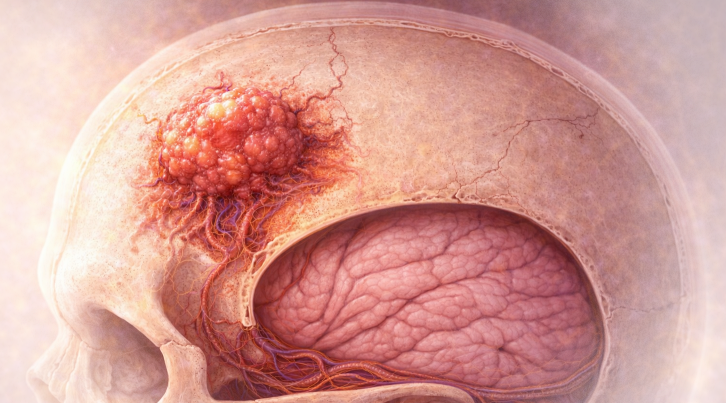

Tumorile craniului osos sunt formațiuni anormale care se dezvoltă din țesutul osos al calotei craniene sau al bazei craniului. Aceste tumori pot fi benigne, cu evoluție lentă, sau maligne, cu potențial invaziv și metastatic. De asemenea, pot fi tumori primare (origine osoasă) sau tumori secundare (metastaze din alte cancere). Deși rare în comparație cu alte tumori osoase, ele au implicații importante datorită proximității față de creier, nervii cranieni și vasele mari.

Metastazele osoase la nivelul craniului apar mai ales în cancerele de sân, prostată, plămân, rinichi și tiroidă.

Pot afecta calota craniană, baza craniului sau orbita.

Simptome: durere locală, deformare, uneori invazie în cavitatea craniană.

- Umflături sau deformări craniene.